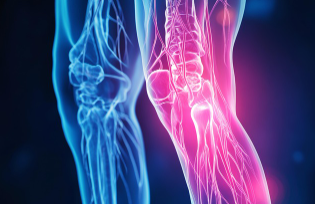

관절은 단순한 움직임의 연결점이 아니라, 우리 몸의 활동성과 삶의 질을 좌우하는 핵심 구조입니다. 그러나 잘못된 생활습관과 무리한 활동은 관절에 부담을 주어 퇴행성 질환을 촉진할 수 있습니다. 이번 글에서는 의학적 근거를 바탕으로 관절을 효과적으로 보호하는 운동 원리와 관절 건강에 도움이 되는 식품을 상세히 소개합니다.

첫째, 관절 주변 근육을 강화하는 근력 운동이 필요합니다. 근육이 약하면 관절이 직접 하중을 받아 손상될 가능성이 커집니다. 예를 들어 무릎 관절을 보호하려면 대퇴사두근, 햄스트링, 둔근을 균형 있게 발달시켜야 합니다.